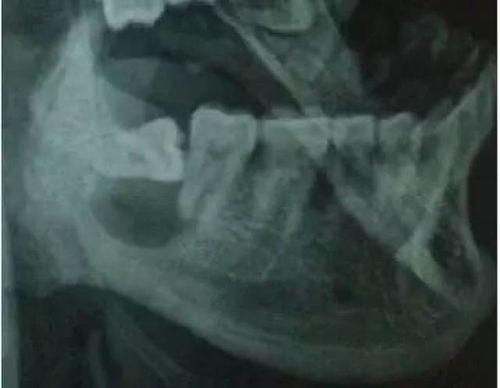

当你走进手术室,你会看到医生们忙碌的身影。他们穿着白大褂,戴着口罩,全神贯注地操作着。这时候,你可能会好奇,他们到底是怎么拔掉智齿的?

别急,让我带你一探究竟。在拔智齿的视频中,你可以看到医生们是如何使用专业的工具,小心翼翼地分离智齿与牙槽骨的连接。他们会用牙挺、牙钳等工具,将智齿从牙槽骨中拔出。整个过程看似简单,但实际上需要医生们丰富的经验和精湛的技艺。